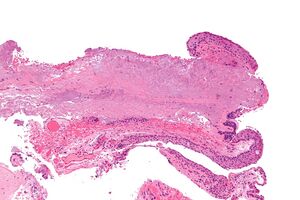

Micrograph of a conjunctiva associated with prominent blood vessels (left-bottom of image) and elastotic collagen (centre of image), as may be seen in a pterygium. H&E stain.

Pterygium in the conjunctiva is characterized by elastotic degeneration of collagen (actinic elastosis[12]) and fibrovascular proliferation. It has an advancing portion called the head of the pterygium, which is connected to the main body of the pterygium by the neck. Sometimes a line of iron deposition can be seen adjacent to the head of the pterygium called Stocker's line. The location of the line can give an indication of the pattern of growth.